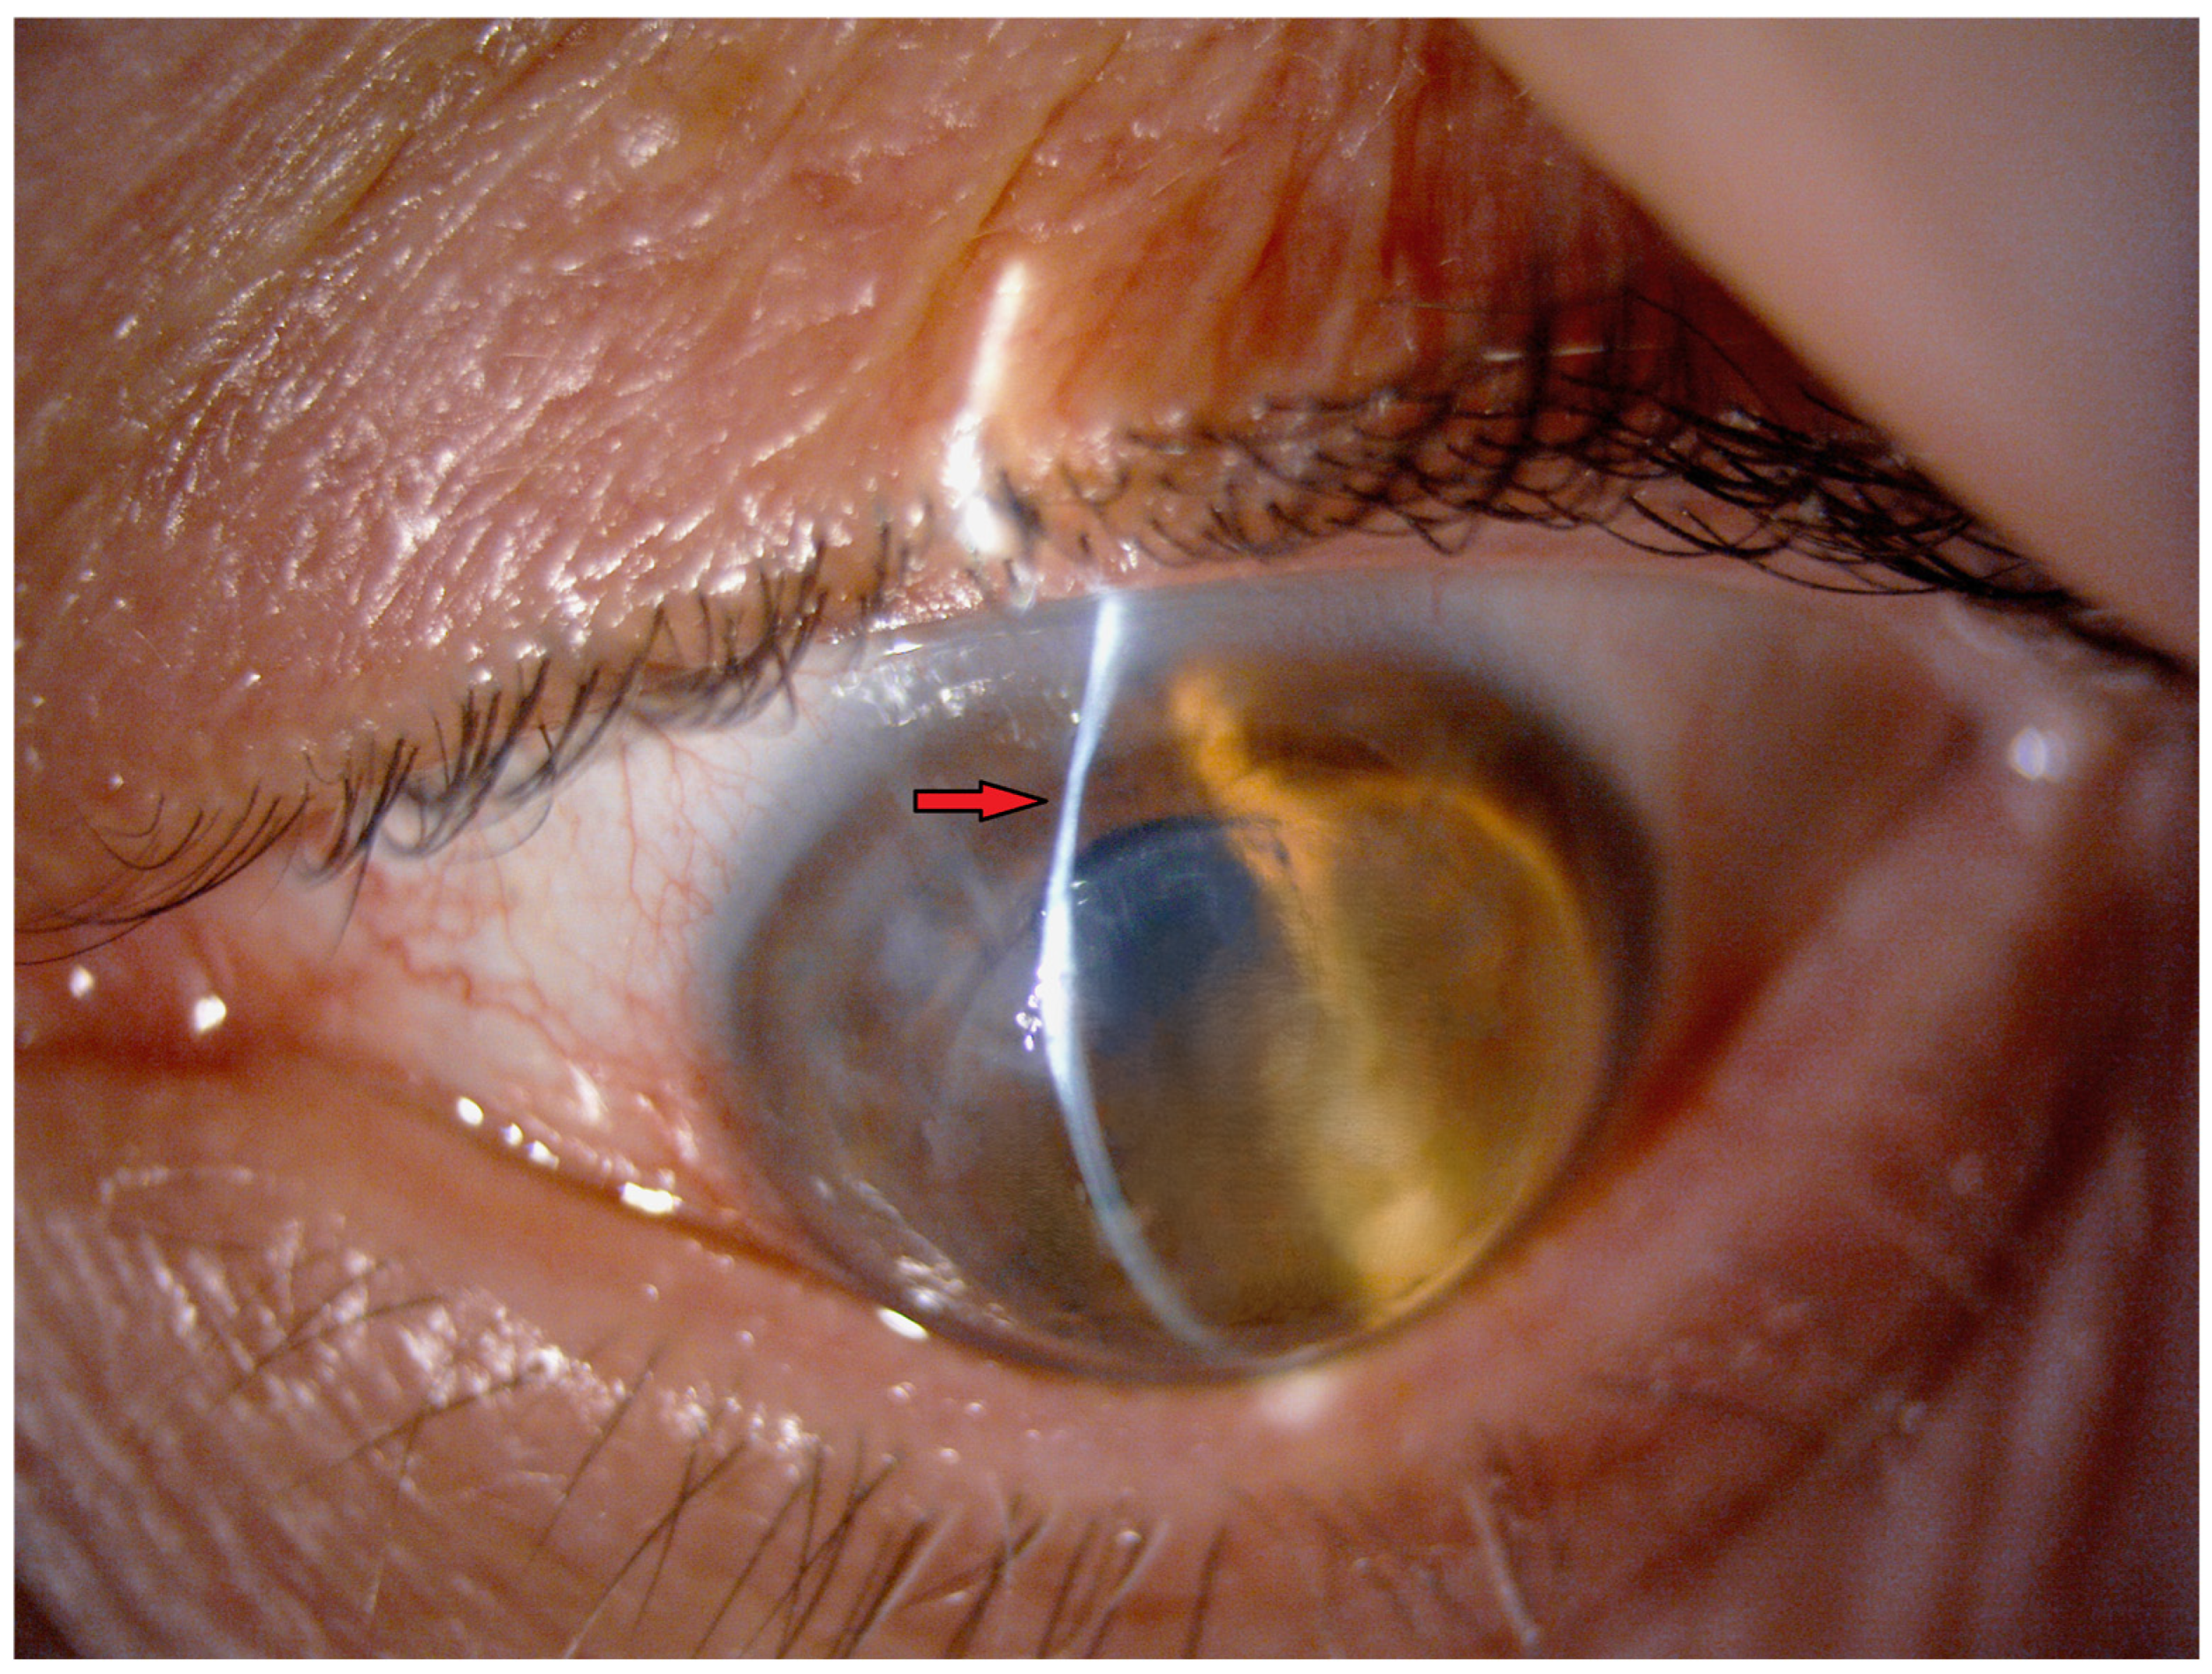

3.1. Preoperative Planning